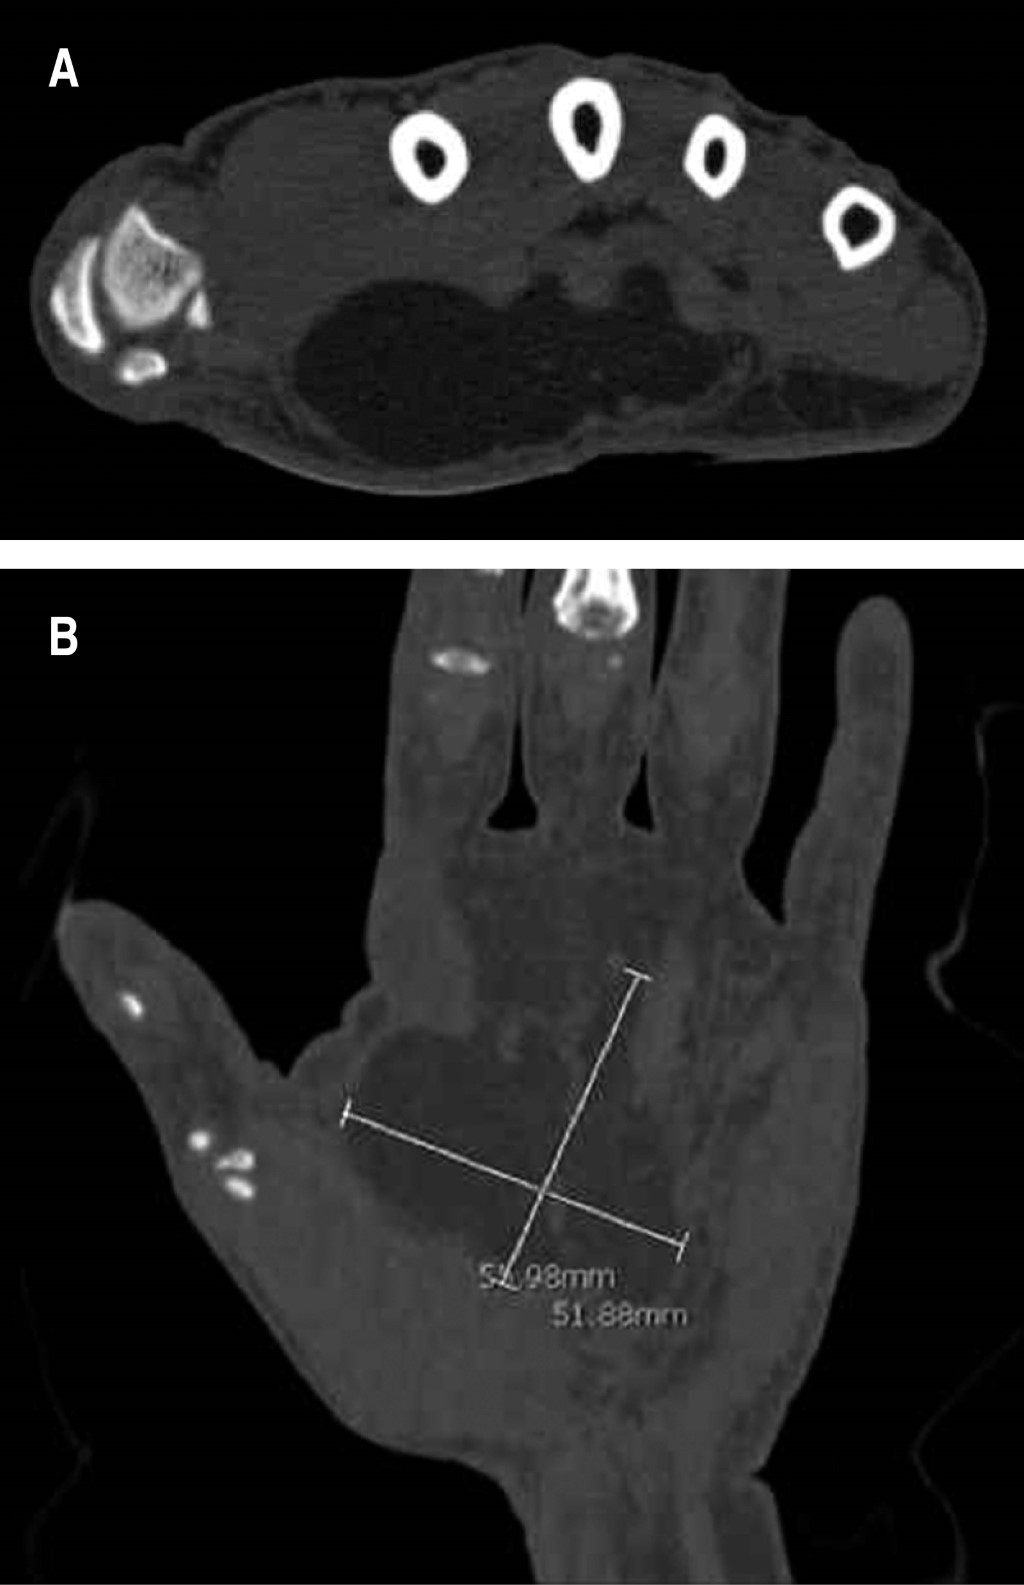

En su valoración se encontró a la exploración de la mano izquierda una tumoración en la eminencia tenar, indolora, de consistencia firme, flexible y relativamente móvil, no adherida a planos profundos. Se realizó transiluminación en la tumoración y fue negativa. No tenía atrofia en la musculatura tenar (Figura 1). A la exploración dirigida se encontró signos de Tinel y Phalen positivos. Se inició protocolo prequirúrgico y se solicitó imagen por resonancia magnética, encontrando en fase T2 imagen homogénea con aumento de intensidad, que reportó probable lipoma en eminencia tenar de 54.98 por 51.88 mm (Figura 2).

Figura 2